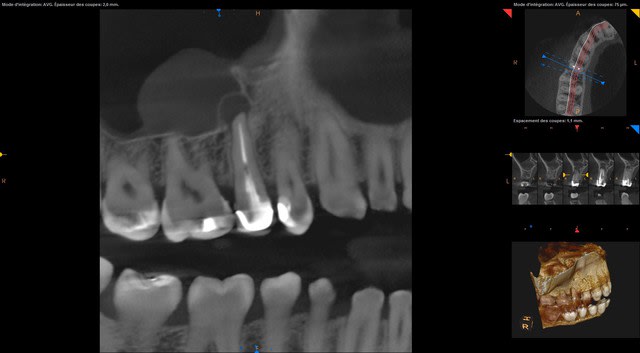

Je vous donne quelques images du cas. C'est pour un comblement per-extraction et eviter une CBS.

Screenshot 1.2.250.1.90.3.1251123212.20151007181521.5252 - Eugenol

Vu le scan il va être quasiment impossible de cureter efficacement, et donc greffer ici est très risqué.